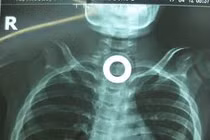

![]() |

| Sau 2 tiếng phẫu thuật, chiếc muống đã được lấy ra ngoài thành công theo cách an toàn là theo đường nó đã đi vào. |

Cô Wang được gây mê và các bác sĩ cố gắng lấy chiếc muống ra dưới sự hỗ trợ của các thiết bị nội soi. Tuy nhiên, ca phẫu thuật gặp nhiều khó khăn do cạnh của chiếc muỗng bo tròn và dạ dày của nạn nhân chứa nhiều thức ăn đã tiêu hóa một phần.

Tiến trình phẫu thuật đã được làm chậm lại để giảm tổn hại tới thực quảng của cô. Cuối cùng, các bác sĩ cũng đã quấn dây, buộc chiếc muỗng lại được và lấy ra ngoài thành công sau khoảng 2 tiếng phẫu thuật.